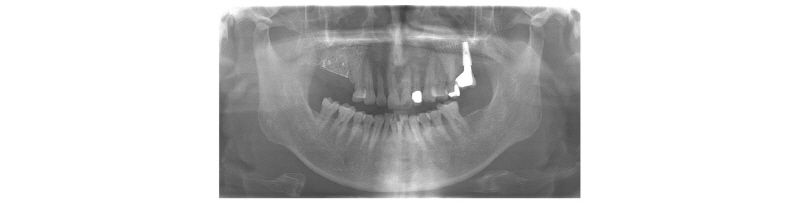

2007년 다른 병원에서 임플란트를 했는데, 임플란트가 빠지고 붓는다는 주소로 내원한 47세 남자 환자이다. 혈압은 다소 높으나, 특별히 약을 먹고 있지는 않는다고 하였고 신경안정제를 복용 중이라고 하였다. 첫 내원 시 우측 하악 구치부 임플란트 보철물은 존재하였으나 3개월 후 다시 재내원했을 때에는 파절되어 빠져 있었다(Fig. 6). 환자와 상의하에 우측 상하악 구치부를 먼저 수복한 후 좌측을 수복하기로 하였다. 우측 상하악 구치부에 남아있는 파절된 임플란트를 제거하였다(Fig. 7). 연조직 치유를 위해서 1달을 기다린 후 우측 하악 구치부 먼저 GBR 시행하기로 하였다. 국소마취 후에 판막을 거상하고(Fig. 8A, 8B), 이종골 이식재(DBBM)을 적용한 후, 비흡수성 차폐막 dense polytetrafluoroethlene (dPTFE)을 덮어주고(Fig. 8C), 4/0 vicryl로 봉합하였다(Fig. 8D). 상악 좌측 구치부는 하악에 비해 재건해야 할 골양이 많아 dPTFE 차폐막을 사용하기 보다는 titanium mesh를 이용하였다. 상악 우측 구치부는 수직적으로 6 mm, 협설방향으로 8 mm, 근원심 방향으로 25 mm 정도의 골유도 재생술을 시행하였고, 하악 우측 구치부는 수직적으로 4 mm, 협설방향으로 8 mm, 근원심 방향으로 20 mm 정도의 골유도 재생술을 시행해 주었다.